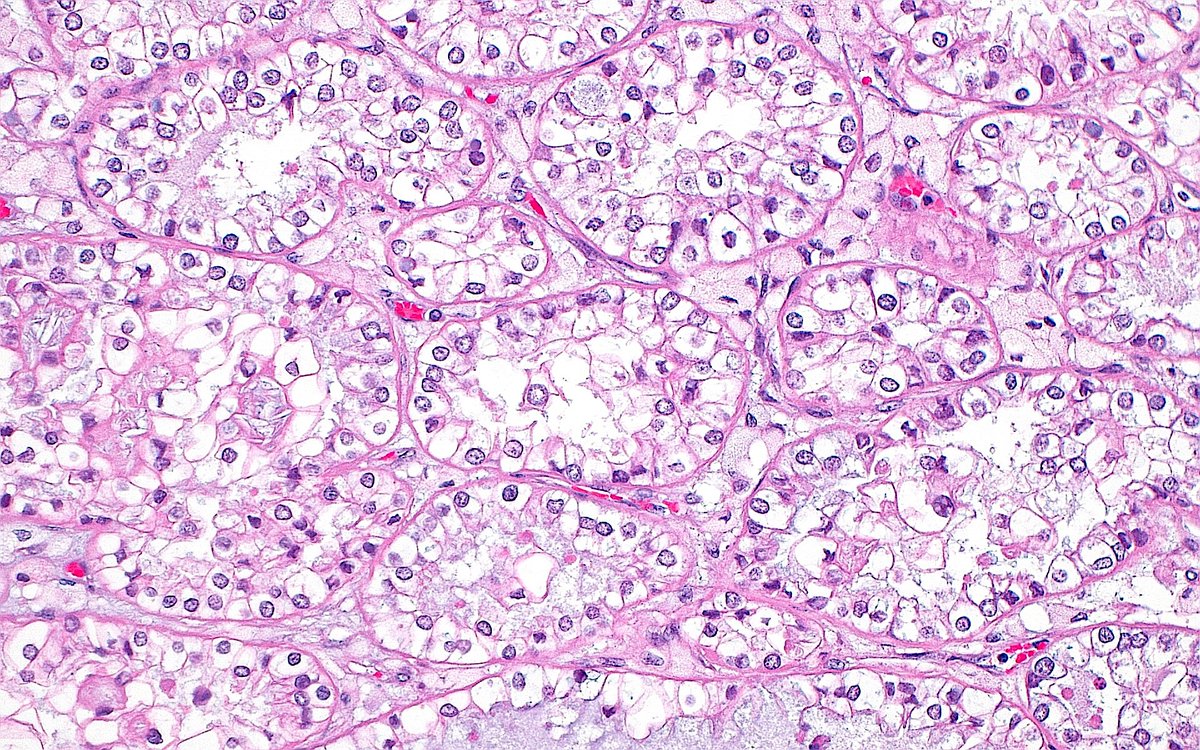

Базофильная аденома